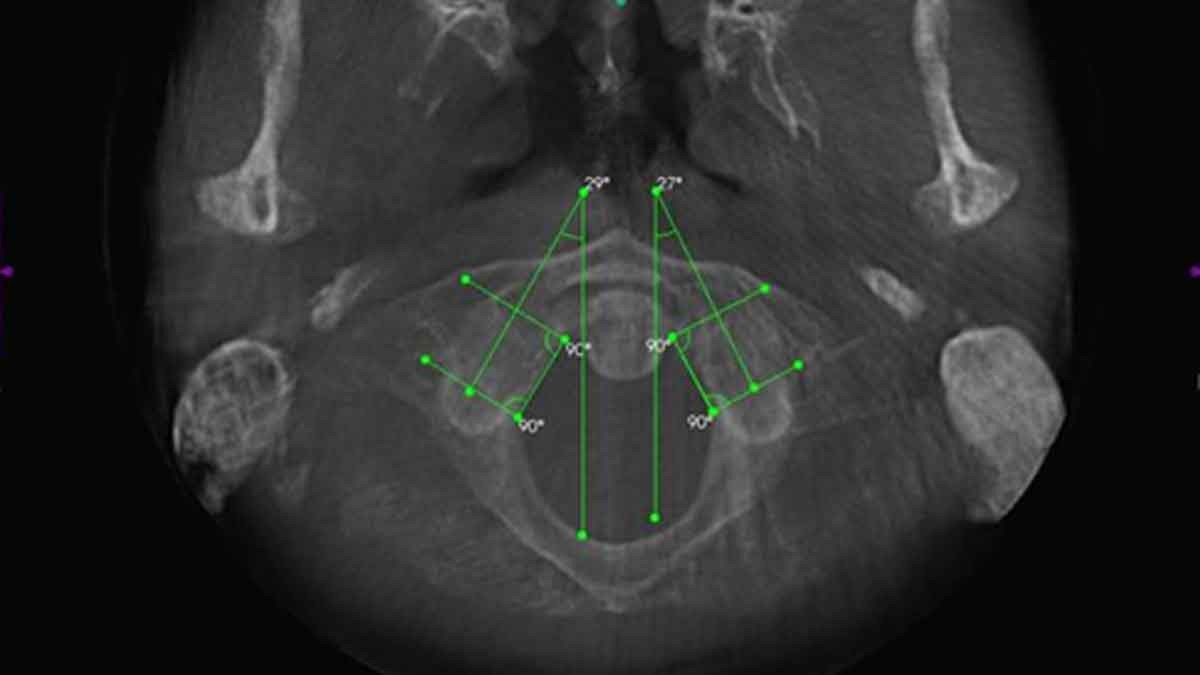

BLAIR PROTRACTO VIEW ON RIGHT BW

This image clearly shows that the c-1 (atlas-arrow) has misaligned to the right and upwards along the joint of the skull above.